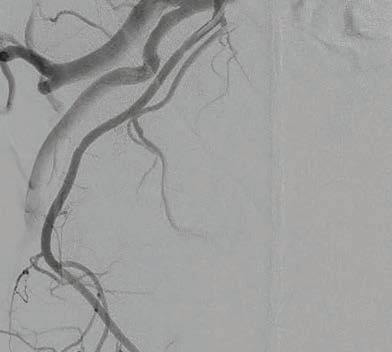

Perth Radiological Clinic offers a comprehensive range of men’s imaging services including:

• Multi-parametric MRI for early detection and staging of prostate cancer

• MRI guided prostate biopsy

• PET-CT PMSA studies

• Penile ultrasound

• Scrotal ultrasound—adult and paediatric

• Urethrograms

• Scrotal interventional procedures

• Cross sectional imaging including MRI for diagnosis and staging of male genitourinary malignancy

• All imaging reported by PRC’s expert sub-specialist urogenital and nuclear medicine reporting teams. Doctor